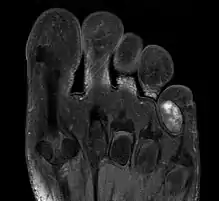

1. IRM d'un chondrome extérieur sur un petit doigt de pied.

Cependant pour le kyste malin, chondrosarcome , on en distingue la malignité par la biopsie et son évolution en cancer en général est suivable avec la radiographie le pet-scan et l'IRM[1].

Celui-ci se présente à l'extérieur ou l'intérieur des os d'articulation (doigts, genou, épaule) parfois sur des côtes et le sternum et les clavicules. S'y ajoute aussi le bassin.